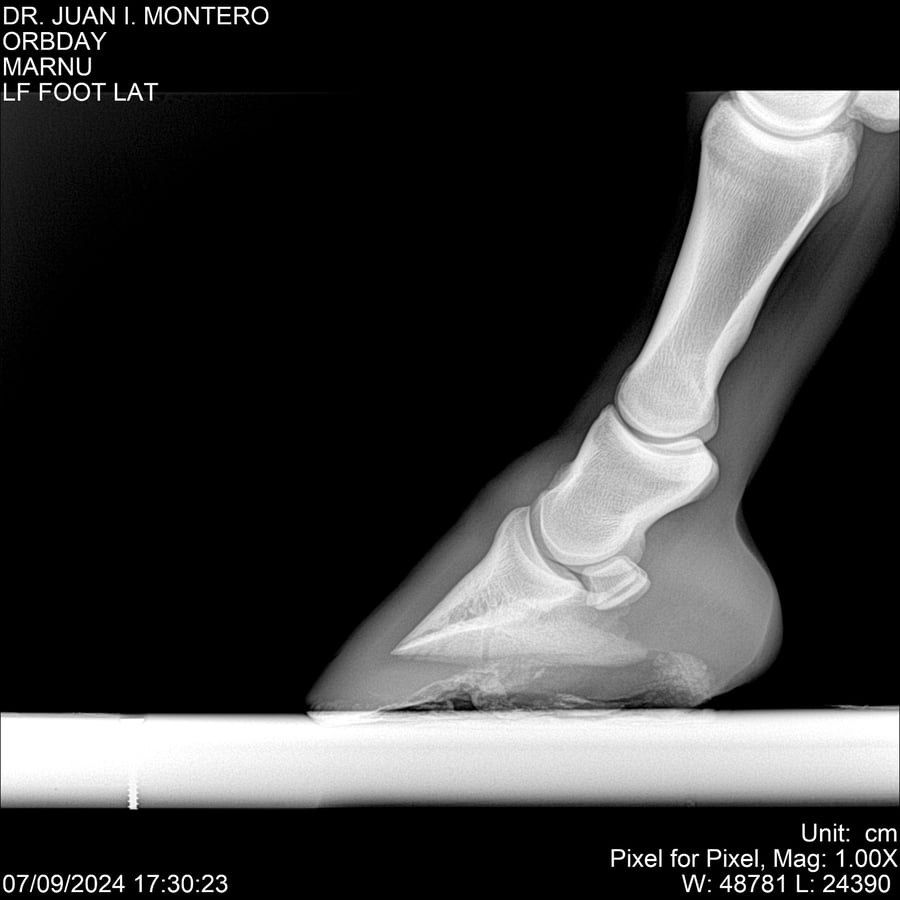

Visualizaciones